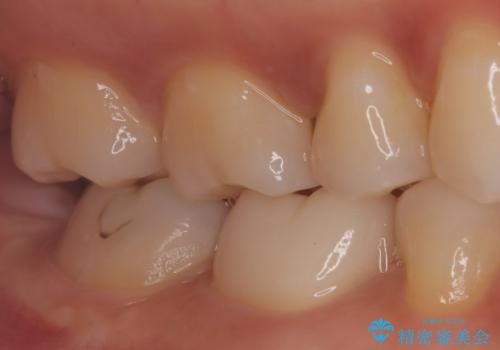

【根管治療】ラバーダムと顕微鏡を用いた治療

- 奥歯の治療の継続を主訴に来院された患者様です。

他院にて根管治療を行ったそうですが、ラバーダムを使用していなかったため、クラウン修復の前に当院の治療を希望され受診されました。

根管内に充填されている材料は、スカスカの状態で簡単に除去ができました。

術後1年経過を見ていますが、問題なく良好な経過をたどっています。